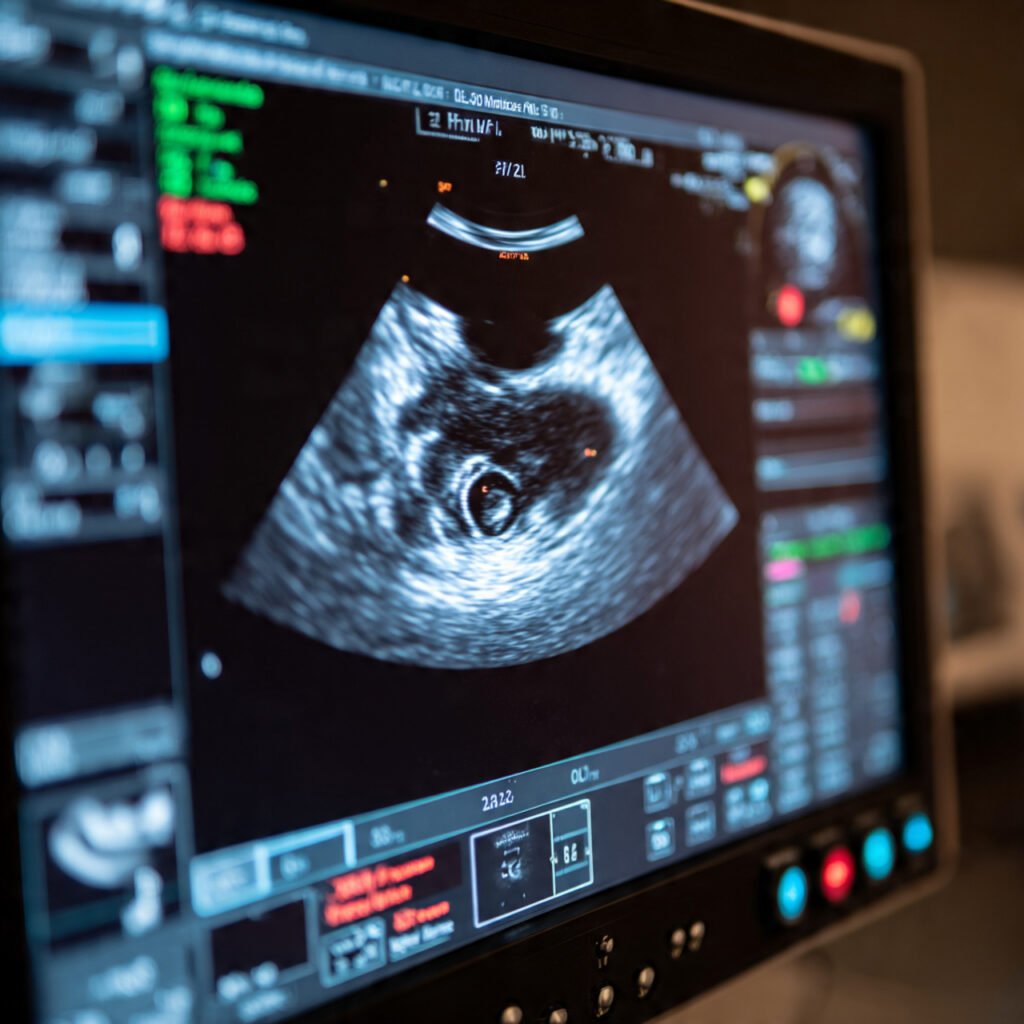

When Does the Baby Show in Early Pregnancy Ultrasound?

During anΒ early pregnancy ultrasound, doctors usually observe:

βœ” Gestational sac (first visible sign)

βœ” Yolk sac (supports embryo development)

βœ” Fetal pole (early embryo)

βœ” Heartbeat (usually seen after 6–7 weeks)

What Is Seen First on Ultrasound?

The earliest structure visible in an early pregnancy ultrasound is:

🟒 Gestational sac – a small fluid-filled structure inside the uterus

As pregnancy progresses, the scan will show:

• Yolk sac

• Fetal pole

• Cardiac activity (heartbeat)